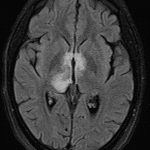

Age: 17

Sex: Female

Indication: Encephalopathy

Case #27

- T2/FLAIR signal hyperintensity in the right greater than left thalami and right greater than left dorsal midbrain with involvement of the periaqueductal gray matter, hypothalamus, anterior commissure, and mamillary bodies

- Areas of cystic change in the right thalamus and right eccentric midbrain

- No corresponding enhancement or restricted diffusion

- No substantial intracranial mass effect or evidence of hydrocephalus

Neuromyelitis optica (NMO)